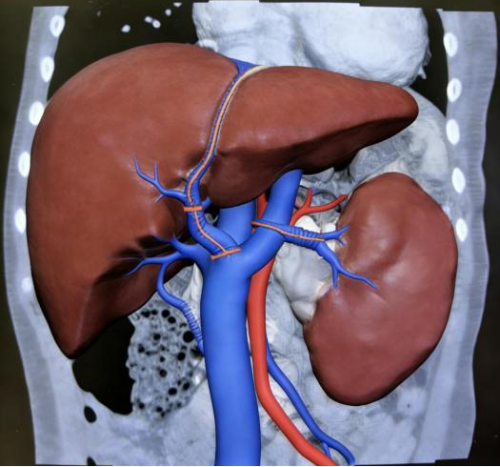

为确保手术万无一失,多学科团队制定了周密的手术方案及应急预案:术前,放射科与超声医学科通过超声及CT血管三维重建,精准评估病变及血管发育情况;消化内科介入团队行选择性静脉造影,绘制"血管地图"精准定位;麻醉科与重症医学科提前做好风险防控,为手术全程保驾护航。

术前CT血管影像评估:门静脉主干阻塞、肝门血管海绵样变、脾大